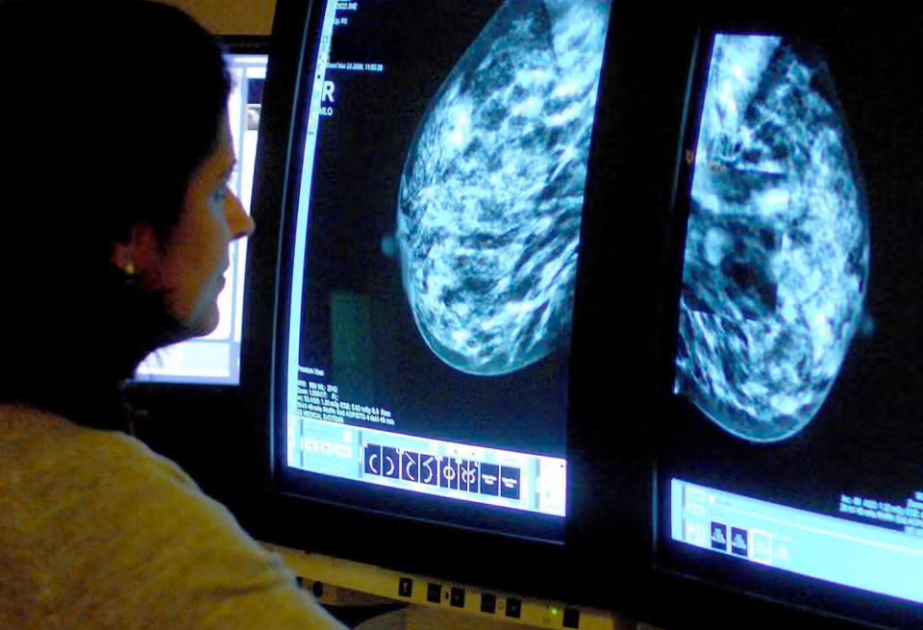

Bugun.tv “The Guardian”a istinadla xəbər verir ki, araşdırmaya görə, 2040-cı ilə qədər ölkədə hər iki dəqiqədə bir nəfərə xərçəng diaqnozu qoyulacaq. Son 15 ildə bu ölkədə 5,5 milyon xərçəng xəstəsi qeydə alınıb. Növbəti 15 ildə isə bu rəqəmin 14,2 faiz artaraq 6,3 milyona çatacağı gözlənilir. Regionlar üzrə ən yüksək artımın cənub-şərq bölgəsində olacağı, 2040-cı ilə qədər burada 1 milyondan çox yeni diaqnozun qoyulacağı ehtimal edilir. “One Cancer Voice” adlı 60 xərçəng xeyriyyə təşkilatını birləşdirən koalisiya hökumətə müraciət edərək, mövcud vəziyyətlə bağlı tədbirlər görməyə çağırıb. Təşkilatlar bildiriblər ki, yalnız bu yolla insanların həyatını xilas etmək və xərçənglə mübarizədə nəticələri yaxşılaşdırmaq mümkündür. Araşdırmaçılar, həmçinin xəbərdarlıq edirlər ki, lazımi tədbirlər görülməsə, Milli Səhiyyə Xidməti bu məsələnin öhdəsindən gəlməkdə çətinlik çəkə bilər.